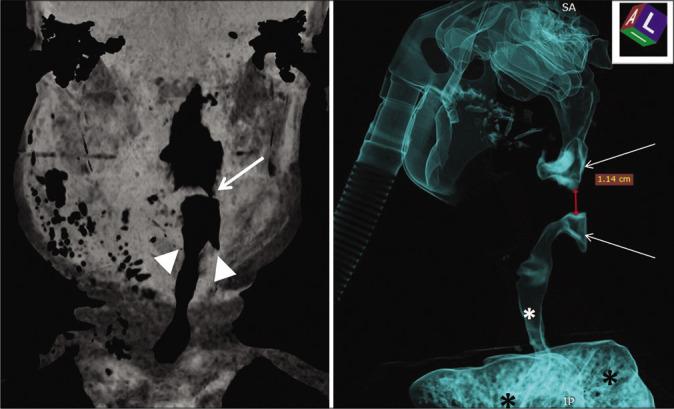

A 60-year-old female with degenerative cervical myelopathy and a previously undiagnosed epiglottic cyst underwent a C5-C6 ACDF; notably, the anesthesiologist found an epiglottic cyst when the patient was first intubated. Two hours postoperatively, the patient acutely developed severe neck swelling with airway obstruction due to angioedema. She was immediately treated with hydrocortisone and required a tracheostomy. The edema decreased markedly in the next 12 h and by the 3 postoperative day it resolved. Three months later, she had no residual medical sequelae.

一名60岁患有退行性颈椎病且此前未诊断出会厌囊肿的女性接受了C5 - C6节段的ACDF手术;值得注意的是,麻醉医生在患者首次插管时发现了会厌囊肿。术后两小时,患者因血管性水肿急性出现严重颈部肿胀并伴有气道梗阻。她立即接受了氢化可的松治疗,并需要进行气管切开术。水肿在接下来的12小时内明显减轻,术后第3天消退。三个月后,她没有残留的医学后遗症。